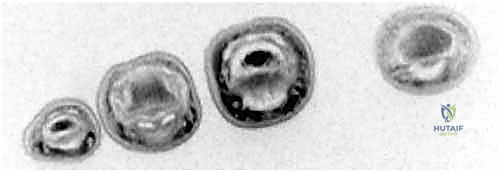

FIG 2 • C. Axial cut MRI at the level of the proximal phalanx shows both FDP and flexor digitorum superficialis (FDS) tendons are present. D. At the level of the middle phalanx, only the FDS tendon can be seen.

Classification of FDP Avulsion Injuries (Leddy and Packard)

This classification guides our urgency and approach:

* Type I: Tendon retracts into the palm. Vinculae are disrupted, leading to poor blood supply. Surgery within 7-10 days is critical.

* Type II: Tendon retracts to the PIP joint or distal A2 pulley. Proximal blood supply via long vincula is preserved. Can be treated successfully up to 6 weeks.

* Type III: Associated with a large bony avulsion, preventing retraction beyond the A4 pulley. Treated as bony injuries with ORIF. Can be treated late.

* Type IV: Bony avulsion where the tendon has also separated from the bony fragment. Time to treatment depends on the level of tendon retraction.